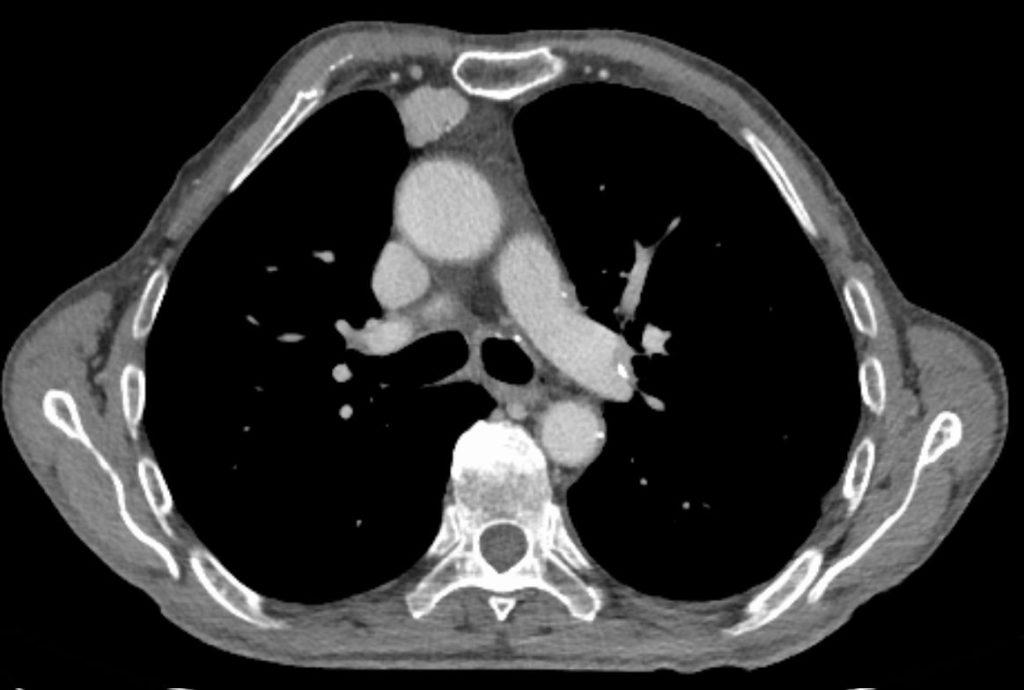

Naïve T cell development in the normal thymus and thymoma. A. A healthy Thymus Autoimmune Thymectomy also appeared be associated with an increased risk of autoimmune disease when patients with preoperative infection, cancer, or autoimmune disease were. Thymomas are counted among the rare tumour entities which are associated with autoimmune disorders (aids) and paraneoplastic syndromes. The thymus is the primary. In this review, we compiled the current scientific evidence detailing the various interactions between thymoma. Thymus Autoimmune.